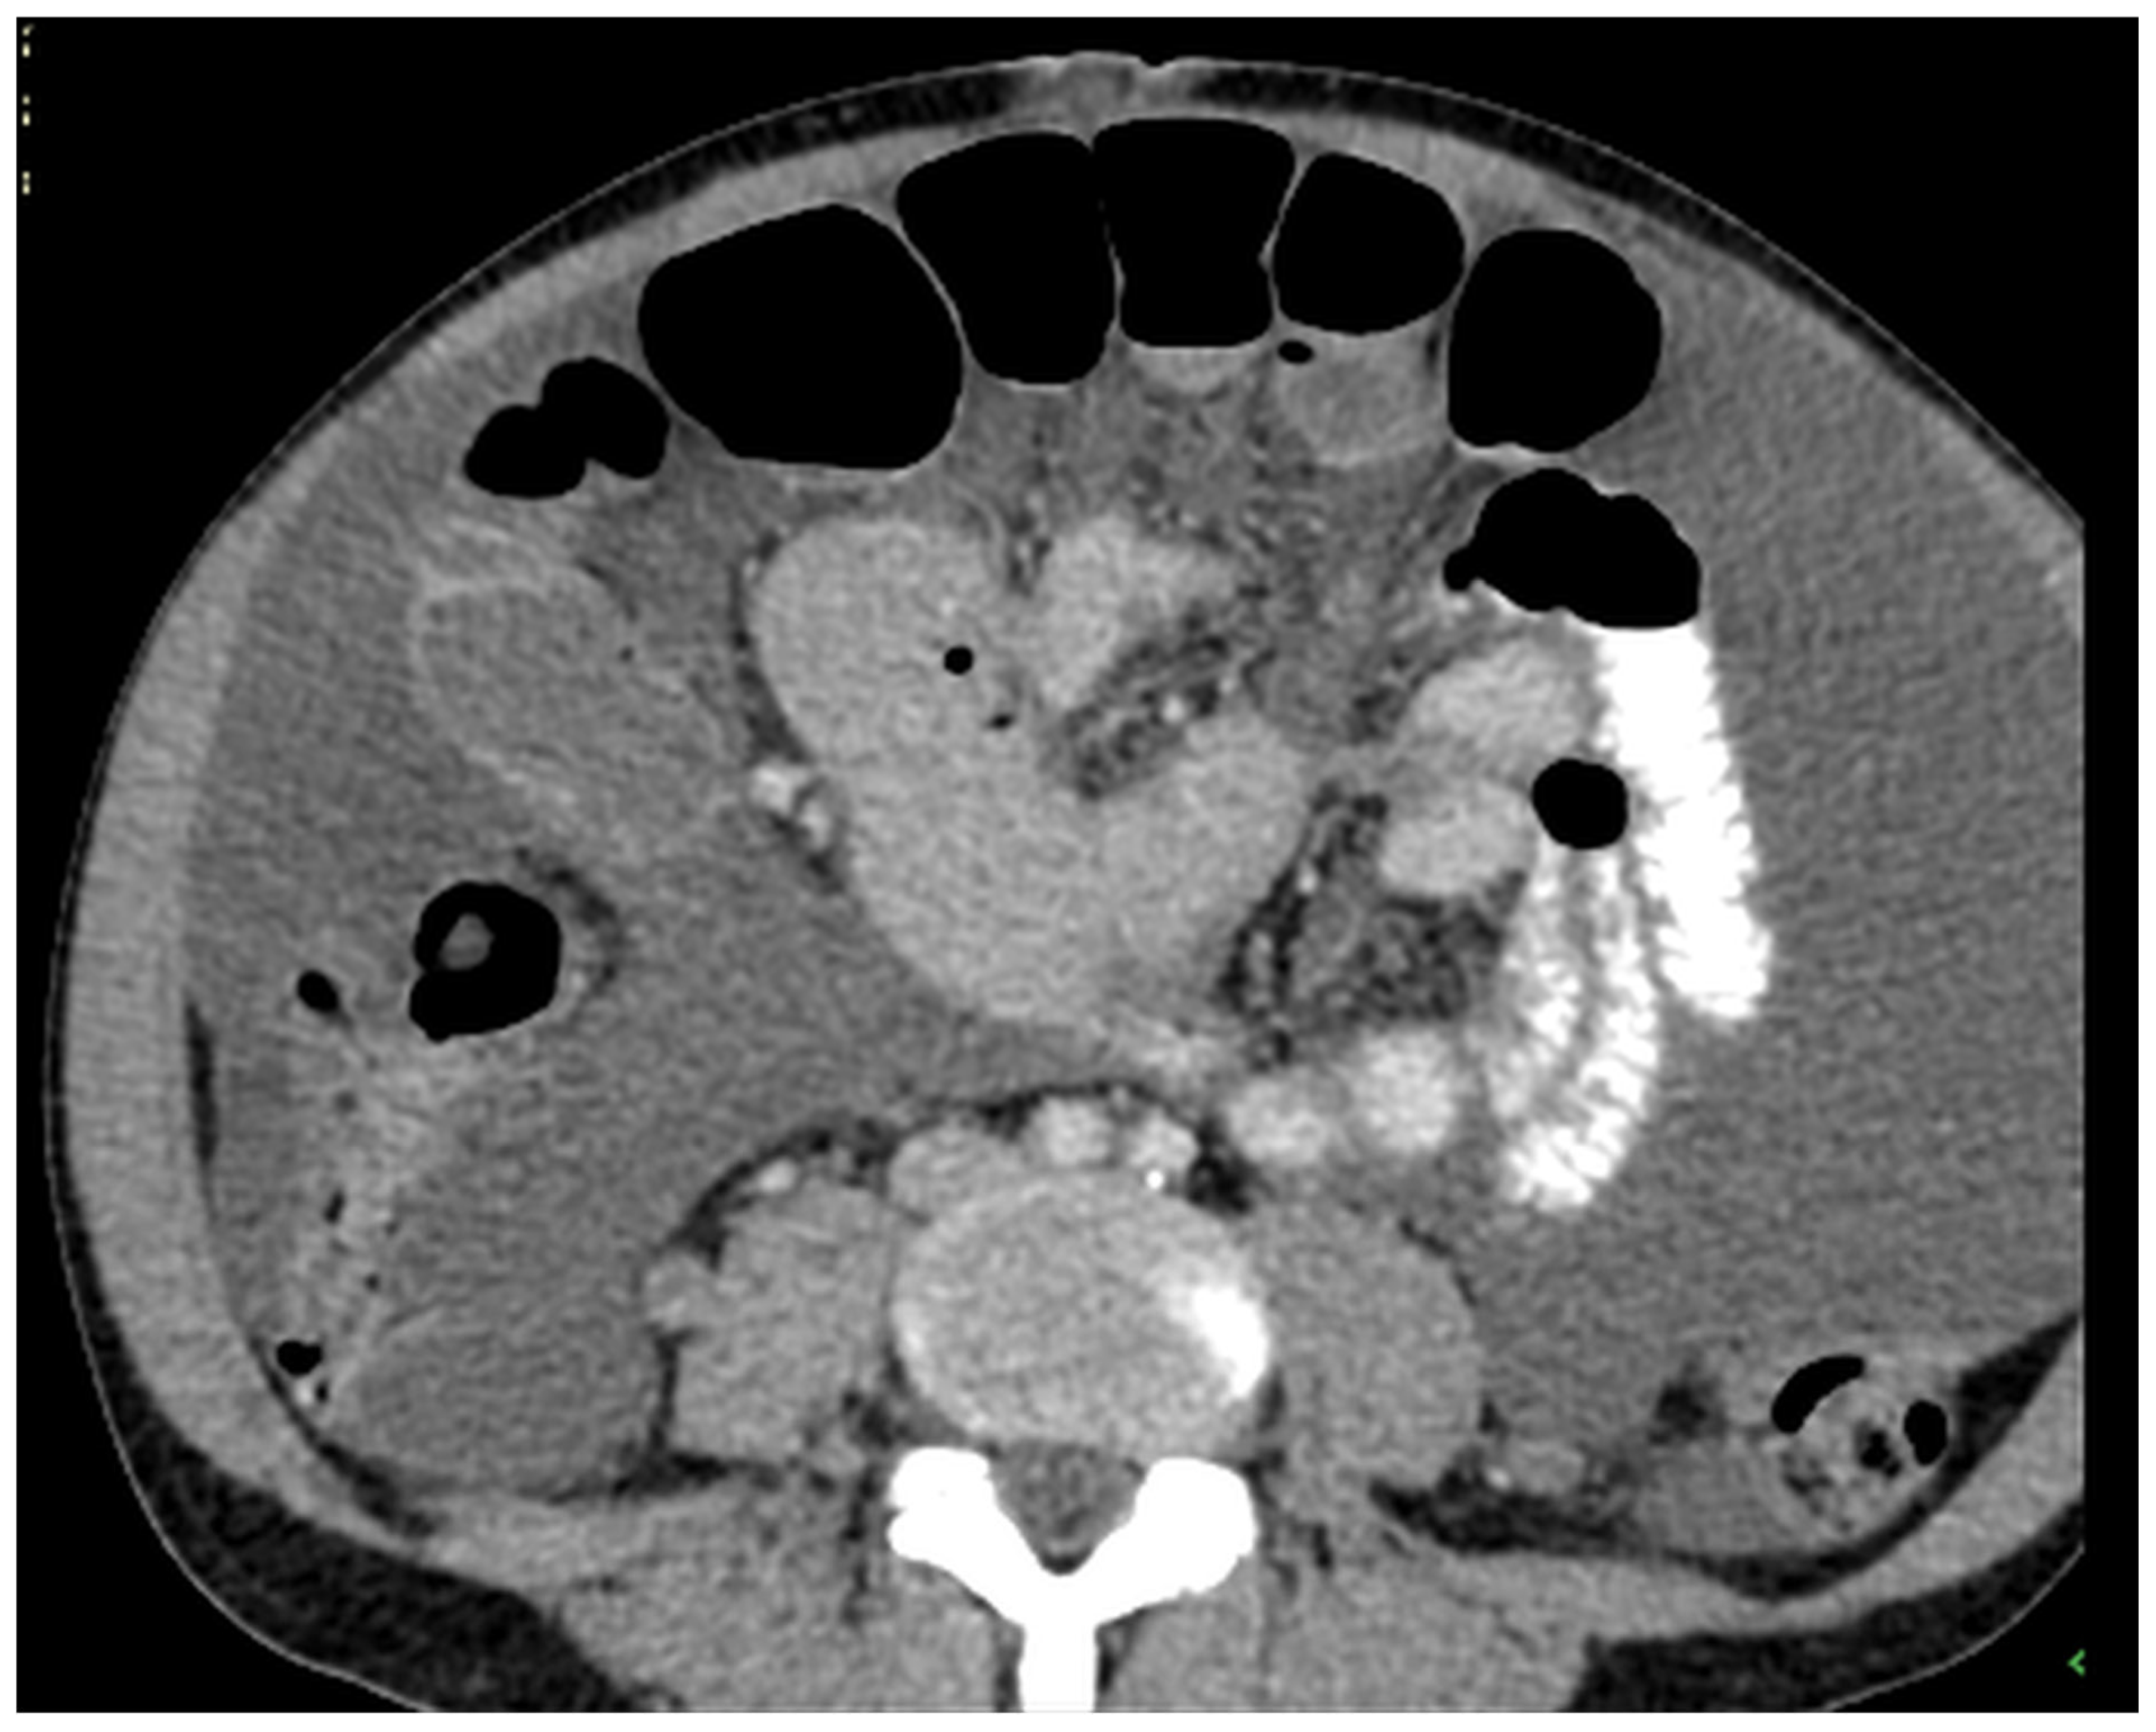

Patients with a misdiagnosed rupture of the mucocele may develop pseudomyxoma peritonei. It is characterized by the presence of an abundant gelatinous substance in the abdomen. Diffuse, progressive, and abundant mucin-containing tumor cells are typical of this disease [2] (Figure 11, Figure 12, Figure 13, Figure 14, Figure 15 and Figure 16). The interval between rupture and advanced disease is several years. In our clinical series, the interval was about 5 years. In the literature, we found a wide range of this interval from 12 months to 10 years [9,10]. The natural history of PMP revolves around the “redistribution phenomenon”, whereby mucinous tumor cells accumulate in the Douglas pouch, in the diaphragm (more on the right), and the small and large omentum (Figure 17). The small intestine is less involved [4]. Pseudomyxoma peritonei is a slowly progressing disease, which fills the peritoneal cavity over time. There are several classifications of pseudomyxoma. The most commonly used is the PSOGI classification [2]. Mucinous accumulation progresses to malnutrition, bowel obstruction, and respiratory compromise. Rarely, the tumor may spread to the pleural cavity. This has been described in 5.4% of cases. It may occur spontaneously or as a result of diaphragmatic injury during cytoreduction [8,11].

Figure 11, Figure 12, Figure 13, Figure 14 and Figure 15. Advanced stage of the disease. The abdomen is full of tumors and mucin. Typical signs are heterogeneous or hypodense masses in the form of lobules often with septa, which could be enhanced by contrast and could be associated with calcifications.

Figure 13. CT, venous phase, axial plane.